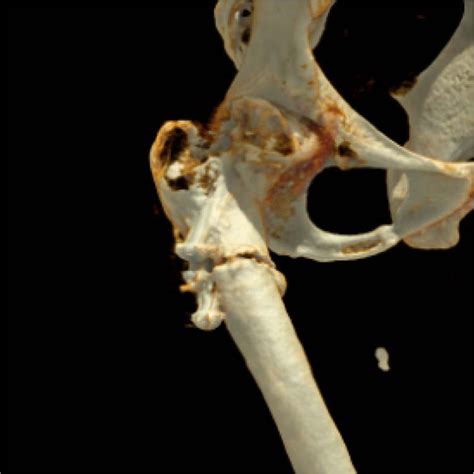

- Tridimensional Reconstruction Of Computerized Tomograph (3d): (a ...